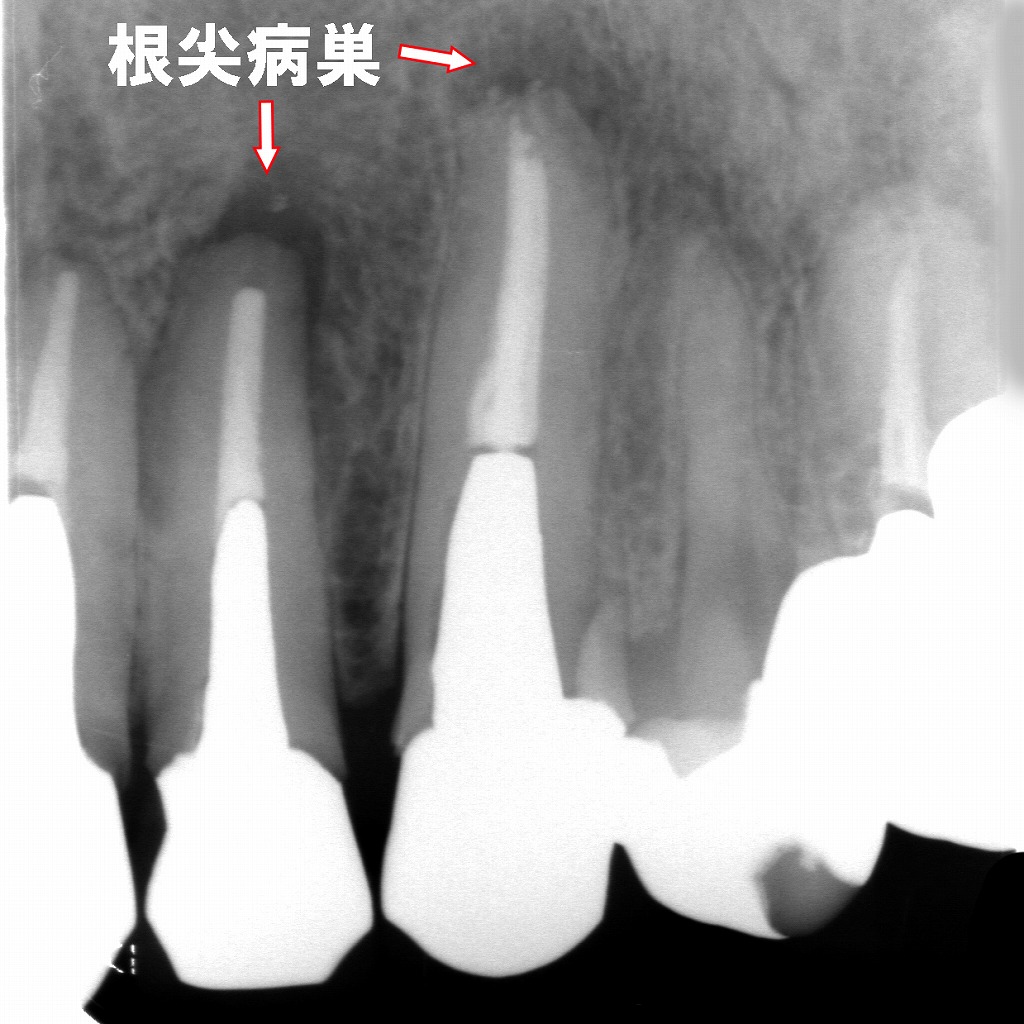

再根管治療後に根尖病巣が治癒

このX線画像は、前回の根尖病巣が治癒した再根管治療後の経過症例を示しています。以下のように説明できます。

🦷 所見の概要

- 対象歯:上顎右側2番(側切歯)・3番(犬歯)

- 画像の特徴:以前認められた根尖部のX線透過像(黒い影)が消失しており、周囲骨の構造が再生していることが確認できます。

- 診断名:根尖性歯周炎の治癒(根尖病巣消失)

このデンタルX線写真は、上顎右側の前歯部(2番・3番)に根尖病巣(こんせんびょうそう)が確認できる症例です。以下に詳細を説明します。

- 対象歯:上顎右側2番(側切歯)および3番(犬歯)

- 根尖部の透過像:両歯の根尖部に黒っぽい(X線透過性の高い)領域があり、これは骨が溶けている=炎症による骨吸収を示しています。

- 診断名:根尖性歯周炎(根尖病巣)